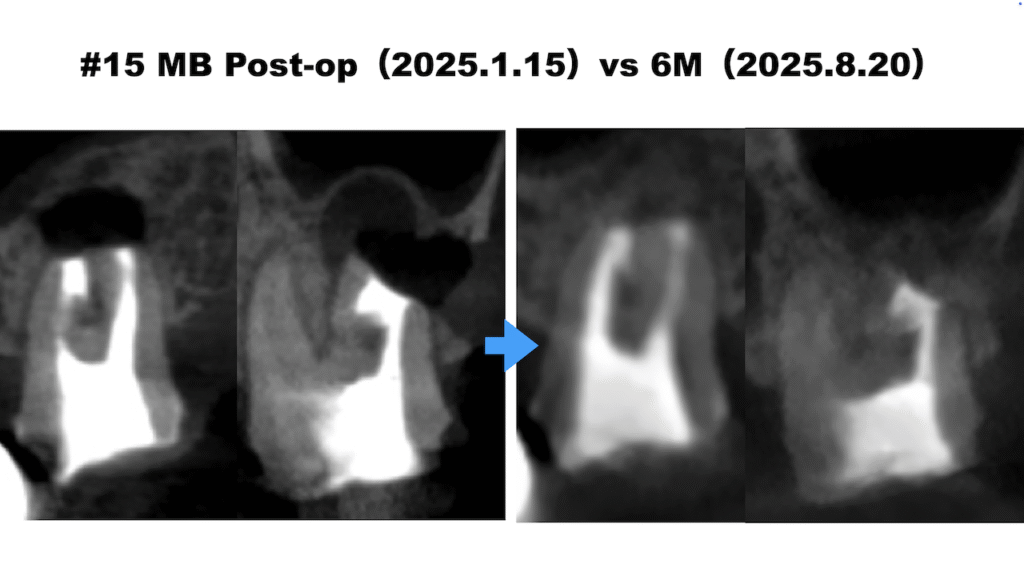

1年半ほど前に地元の歯科医院で治療を続けてきたが良くならず、今も咬合痛がある。痛みなく、普通に食事ができるようになりたい。。。〜#15 MB+DB Apicoectomyとその6M recall

昨日の記事の続報。 再根管治療が奏功しなかったので、#15(左上第2大臼歯)のMB+DBのApicoectomyを行うことになったCaseである。 別日に外科治療が行われた。 その内容だがそもそもどうやってそんなことをす … 続きを読む 1年半ほど前に地元の歯科医院で治療を続けてきたが良くならず、今も咬合痛がある。痛みなく、普通に食事ができるようになりたい。。。〜#15 MB+DB Apicoectomyとその6M recall